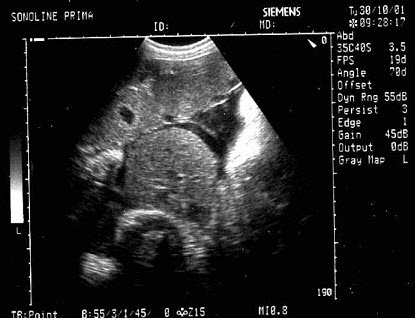

17、单项选择题

男,64岁,右上腹反复疼痛不适数10年,加重5天。声像图如图所示,诊断为()

A.肝内钙化带

B.胆囊充满型结石并萎缩性胆囊炎

C.胆囊蛔虫

D.肠襻回声

E.胆囊癌